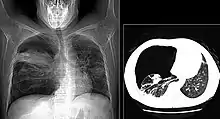

The diagnosis can be confirmed by the characteristic appearance of the chest X-ray and an arterial oxygen level (PaO2) that is strikingly lower than would be expected from symptoms. Gallium 67 scans are also useful in the diagnosis. They are abnormal in about 90% of cases and are often positive before the chest X-ray becomes abnormal. Chest X-ray typically shows widespread pulmonary infiltrates. CT scan may show pulmonary cysts (not to be confused with the cyst-forms of the pathogen).

Chest X-ray of increased opacification (whiteness) in the lower lungs.